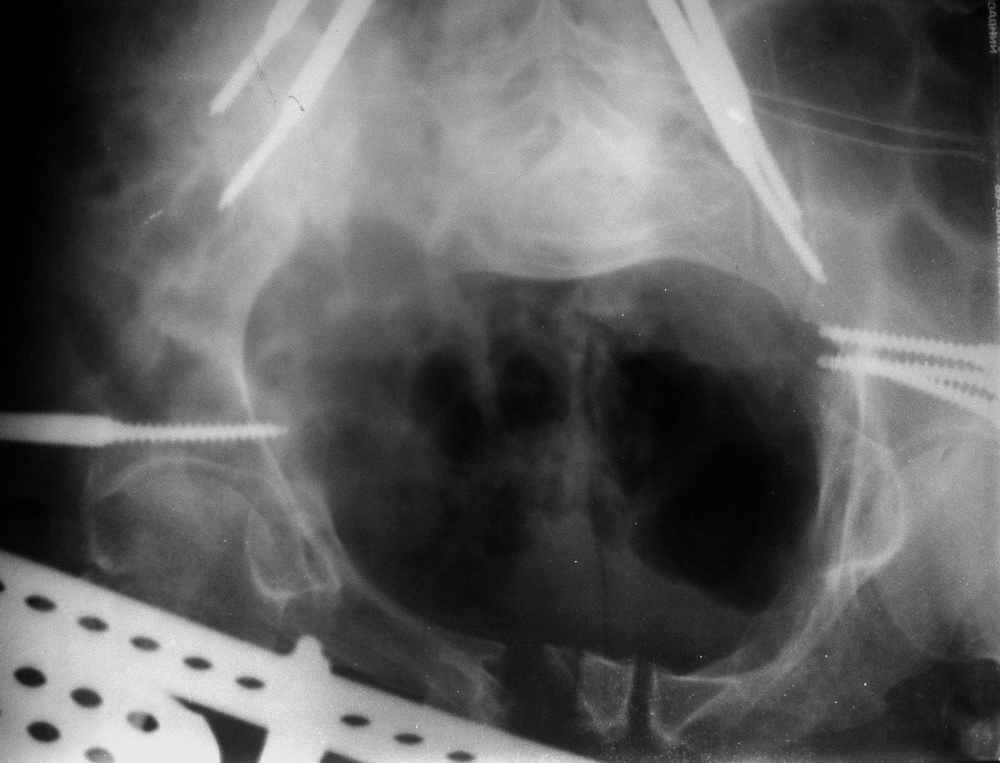

Исходная картина

отеотомия передних и задних отделов, дистракция аппаратом